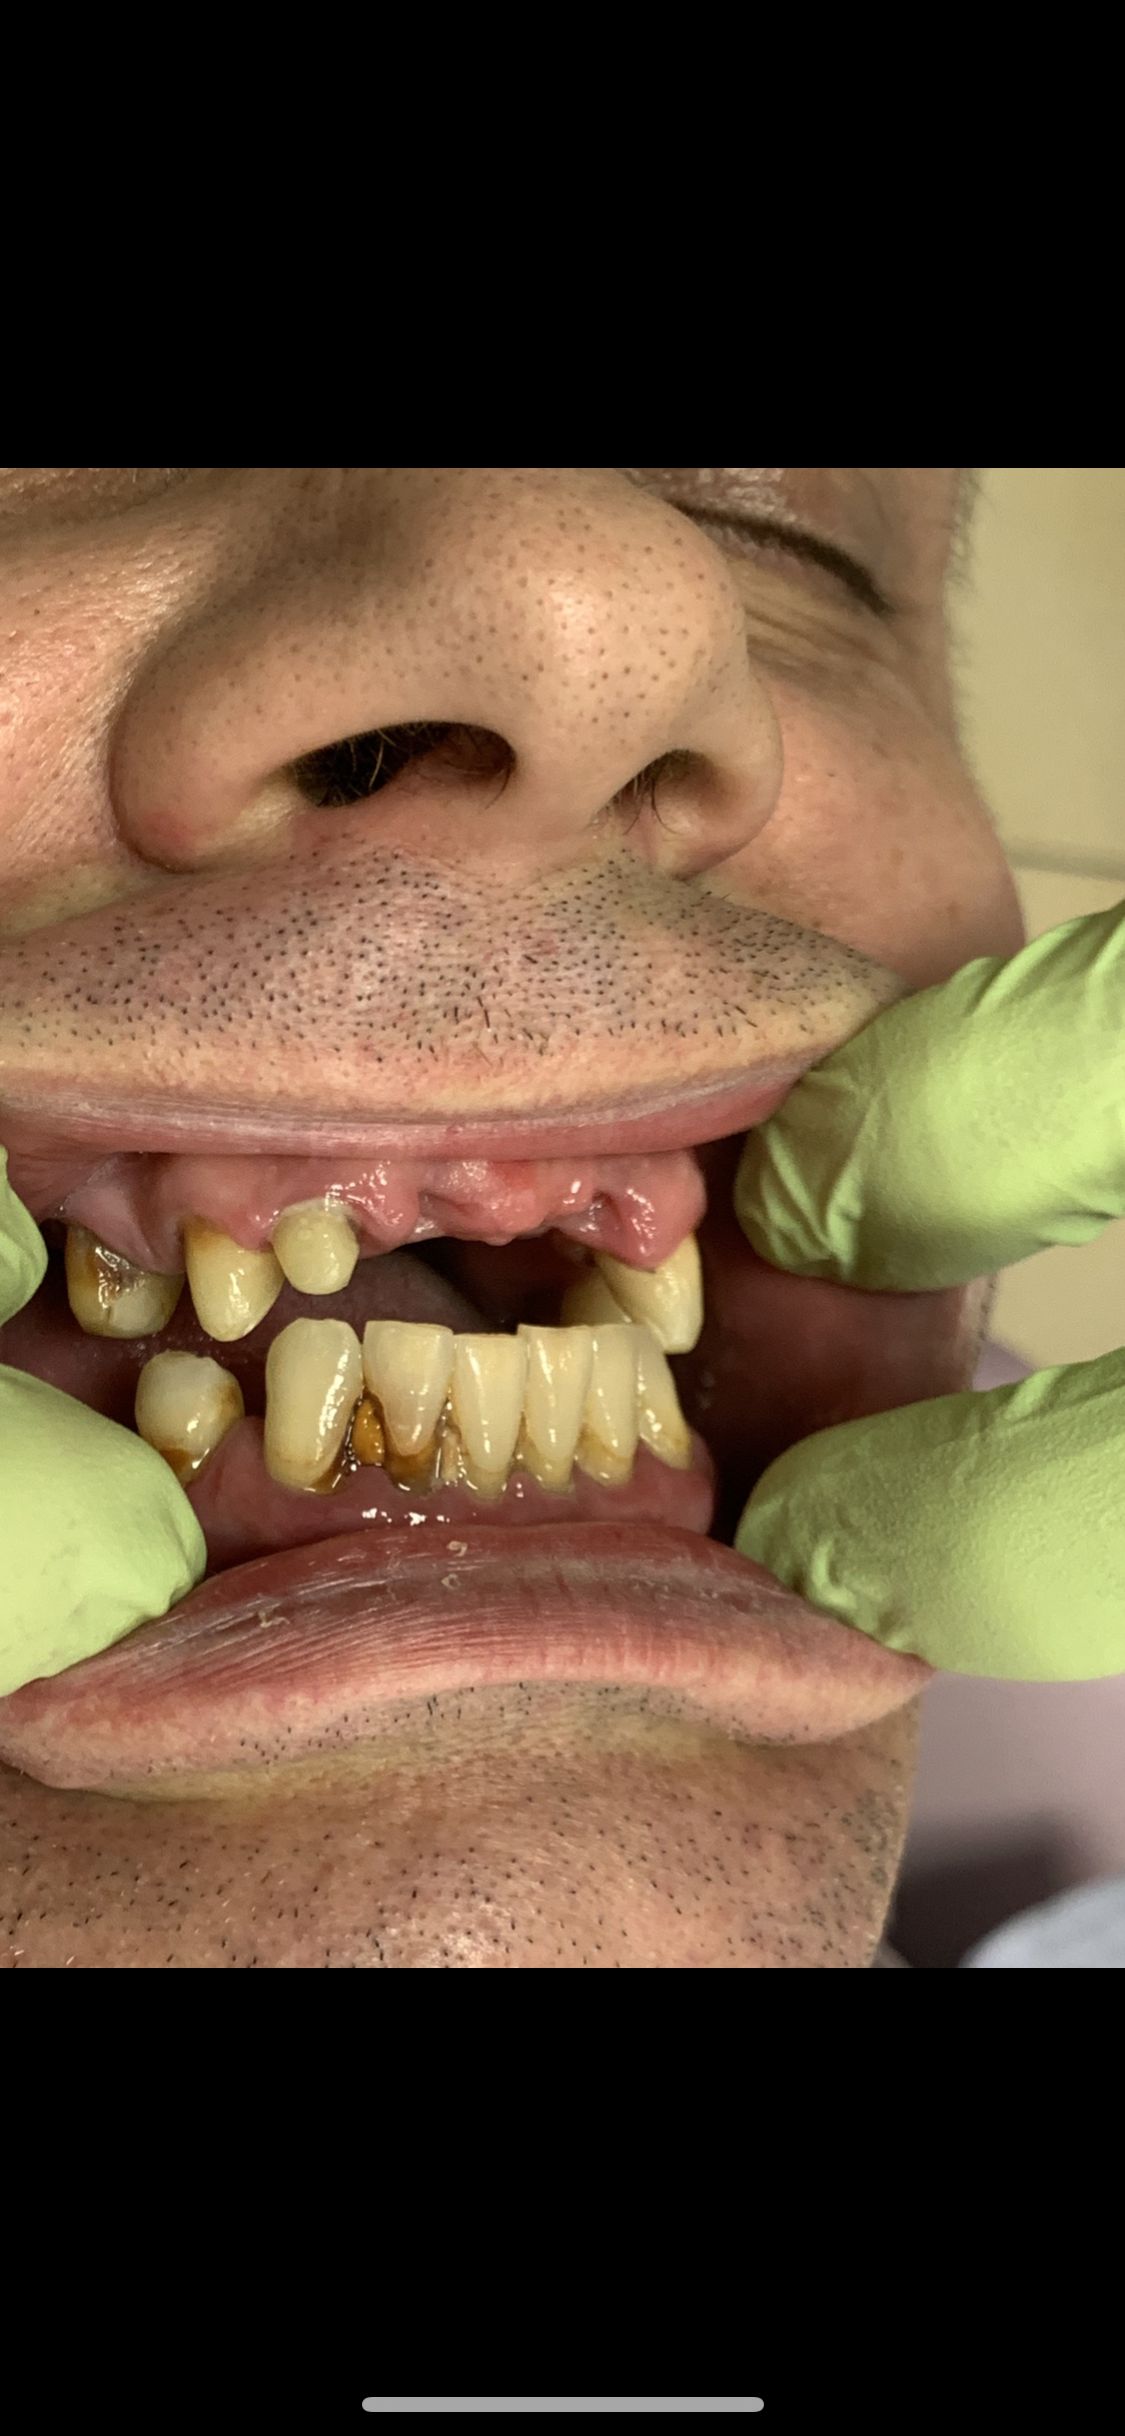

Ukończyłem Łódzką Akademie Medyczna, na wydziale stomatologicznym . W 2007 roku uzyskałem tytuł specjalisty w dziedzinie protetyki stomatologicznej. Regularnie pogłębiam wiedze z zakresu stomatologii o czym świadczą zdobyte przeze mnie certyfikaty . W chwili obecnej prowadzę NZOZ Duodent , specjalistyczny gabinet protetyczny na Widzewie - wschodzie , przy ul. Gogola 12 . Znajdują sie tu trzy nowocześnie urządzone i wyposażone gabinety stomatologiczne. Pracujemy na sprzęcie Sterna Webera, prestiżowej szwajcarskiej firmy produkującej unity stomatologiczne...W gabinecie znajduje sie skaner wewnątrzustny MEDIR i 500 R , gdyz obecnie gabinet nasz wyspecjalizował sie w PROTETYCE CYFROWEJ

Z pełnym przekonaniem polecam leczenie protetyczne w tym gabinecie. Wykonane korony porcelanowo-cyrkonowe spełniły moje oczekiwania zarówno pod względem estetycznym, jak i funkcjonalnym. Efekt końcowy jest bardzo naturalny, korony są idealnie dopasowane i komfortowe w codziennym użytkowaniu. Cały proces leczenia przebiegał sprawnie, z dokładnym omówieniem planu oraz poszczególnych etapów. Lekarz wykazał się dużą wiedzą, precyzją i dbałością o detale, co w protetyce ma kluczowe znaczenie. Dodatkowo czułem się zaopiekowany i spokojny, co zdecydowanie podnosi komfort leczenia.

• Duo-Dent korony cyrkonowe  •